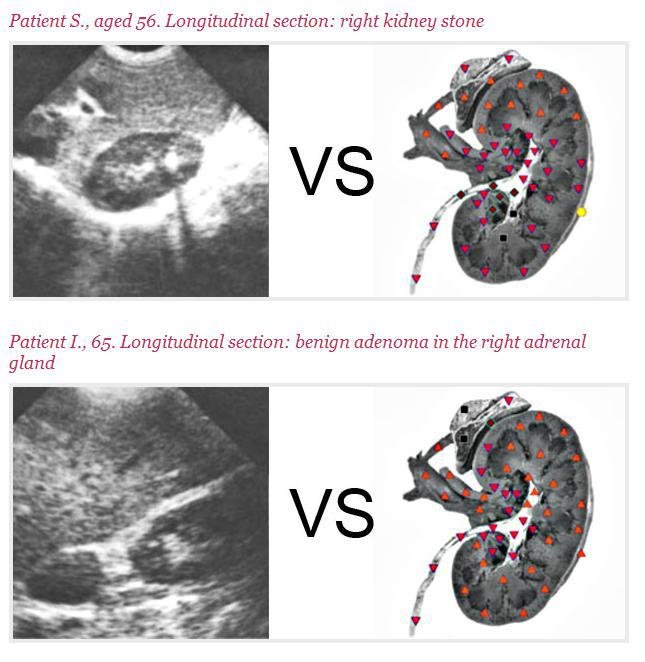

The Dolma 8D NLS performs biofield analysis for organ biofields, the cellular biofield level, chromosomal biofield level and microorganism biofield level. Others have characterized the accuracy of the Dolma 8D NLS to have an accuracy between 80 – 95%.